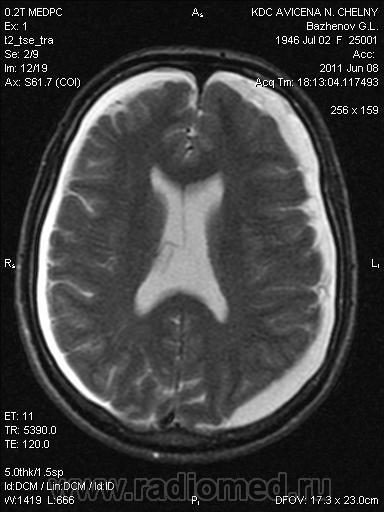

Двусторонние субдуральные гематомы.

Конечно, субдуралки. Несвежие.

На днях был абсолютно идентичный случай. Написал двусторонние гигромы, что подразумевает несвежие субдуральные гематомы, хотя и не исключает другие варианты.

Это не гематомы.

Извините, unre_ALL, но у Вас совершенно неправильные представления о субдуральных гематомах. Гигромы в суставах - это из дугой "оперы". Хронические субдуральные гематомы - это скопление жидкости (которая раньше была кровью и гемолизировалась). Изредка субдуральная гематома может рассасываться полностью, но очень редко. Кровотечение при субдуральных гематомах из вен, в отличии от эпидуральных, поэтому они более благоприятно протекают, чем эпидуральные. Наличие переломов совершенно не обязательно. Подкожные гематомы могли и рассосаться с января месяца. Если пациент в возрасте, травма не обязательна. В данном случае сигнал как от жидкости с довольно высоким содержание белка. По сигналу это не ликвор (сравните с ликвором в желудочках). Лимфома все же менее вероятна, чем гематомы. Я бы отправила к нейрохирургу как можно быстрее.